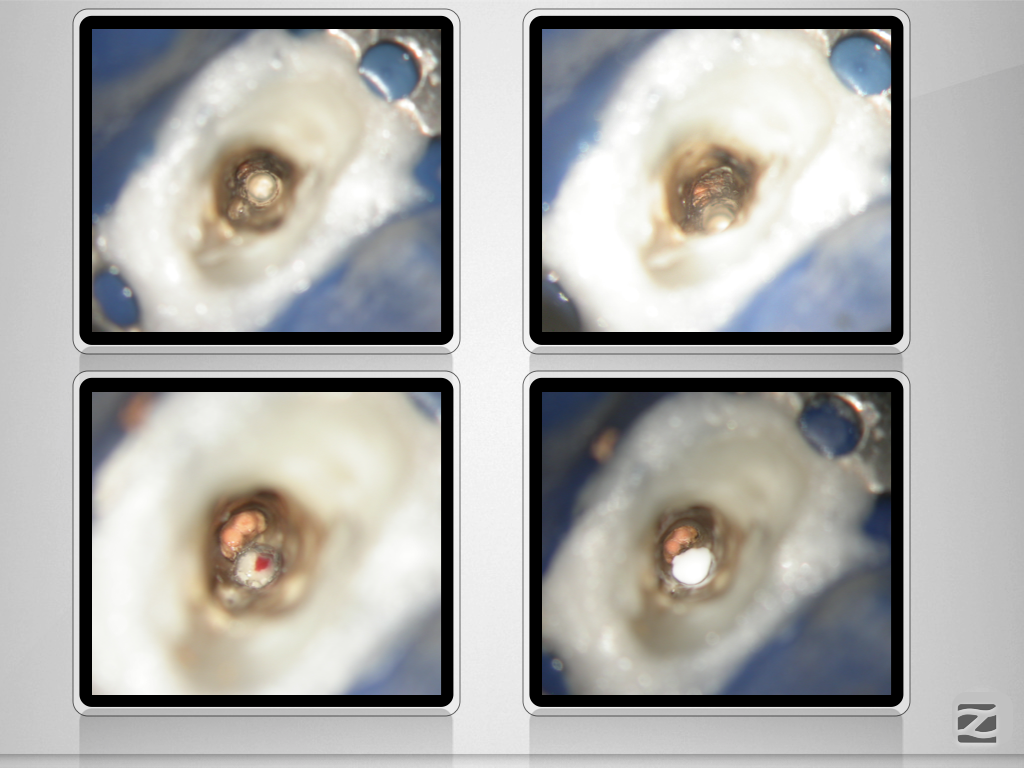

13D.009 Veröffentlicht 21. Januar 2020 am 1024 × 768 in Wer hat Angst vor’m bösen Stift? Teil 2, Zirkonoxidstift